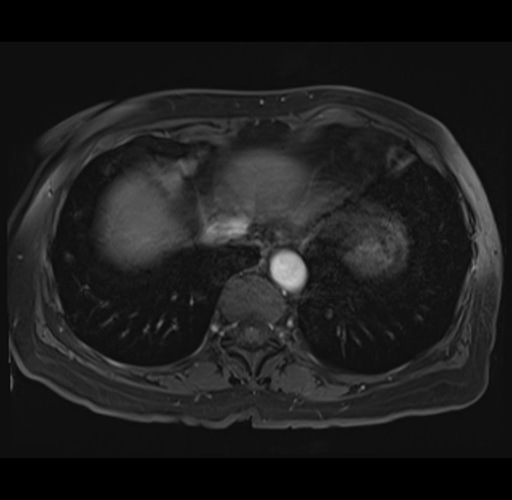

MRI T1

Imaging analysis

Based on your CT findings, which issue(s) would give reason for "planned slowing down moment(s)" in this case?

Considering a standard right hepatectomy procedure, what step(s) of the operation would you do differently in this case?